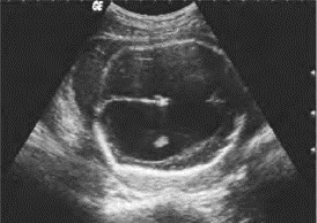

1.38.12十二、胎儿畸形